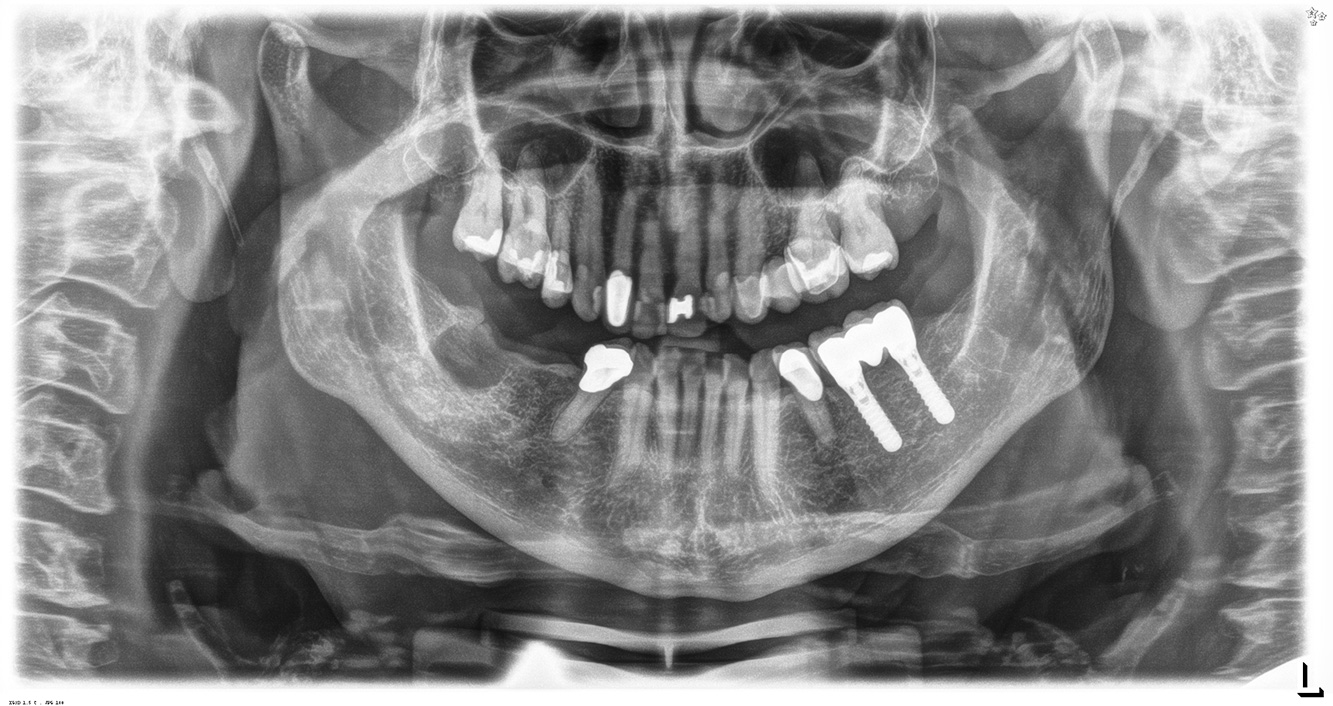

The (orally) healthy patient with implants

In the medical history, the 55-year-old patient states that he has no systemic disease and is not taking any medication. The patient’s lifestyle is similarly unremarkable. The patient has a few tooth restorations and two implants (2nd and 4th quadrants). On the basis of current findings, gingivitis is identified in an otherwise stable periodontal condition on the reduced periodontium (stage III, grade A). more

The healthy patient with pre-existing periodontal disease & peri-implantitis

A 52-year-old patient presents at a preventive care session. The patient has no systemic disease and is not taking any medication. He has had various dental treatments and also has two active carious lesions. In addition, the patient has four implants (2nd, 3rd and 4th quadrants). He is revealed to have early periodontal disease (stage IV, grade B). His periodontal condition is stable; a probing depth of Probing depths (ST) of 5 mm is only evident at the implant in region 36. Gingivitis is also identified. more